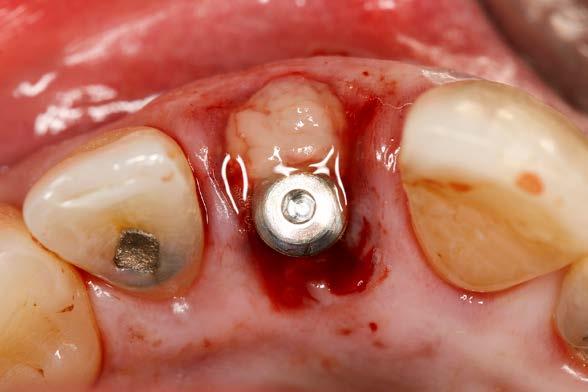

posible sobre los tejidos blandos y sobre el hueso remanente (Figura 5 y 6). Procedemos posteriormente a realizar una secuencia de fresado adaptada al lecho postextracción, alargando el alveolo con las fresas apicalmente y hacia palatino, donde se producirá el anclaje del implante. Con el lecho preparado colocamos el implante, quedándonos en vestibular el gap esperado de aproximadamente 4 mm como podemos ver en la

Figura 7. La utilización de un implante de longitud mayor y la inclinación hacia palatino nos permite lograr la estabilidad primaria necesaria para poder llevar a cabo una carga inmediata del implante. Una vez finalizada la inserción colocamos el transepitelial unitario para trabajar sobre el mismo generando la prótesis provisional de carga inmediata. Esta pieza intermedia (implante-prótesis) nos permite el uso de una interfase,

Figura 7. Imagen tras la colocación del implante ligeramente palatinizado con el gap situado en vestibular.

Figura 8. Imagen del implante colocado en el alveolo con el transepitelial unitario para llevar a cabo la carga inmediata.